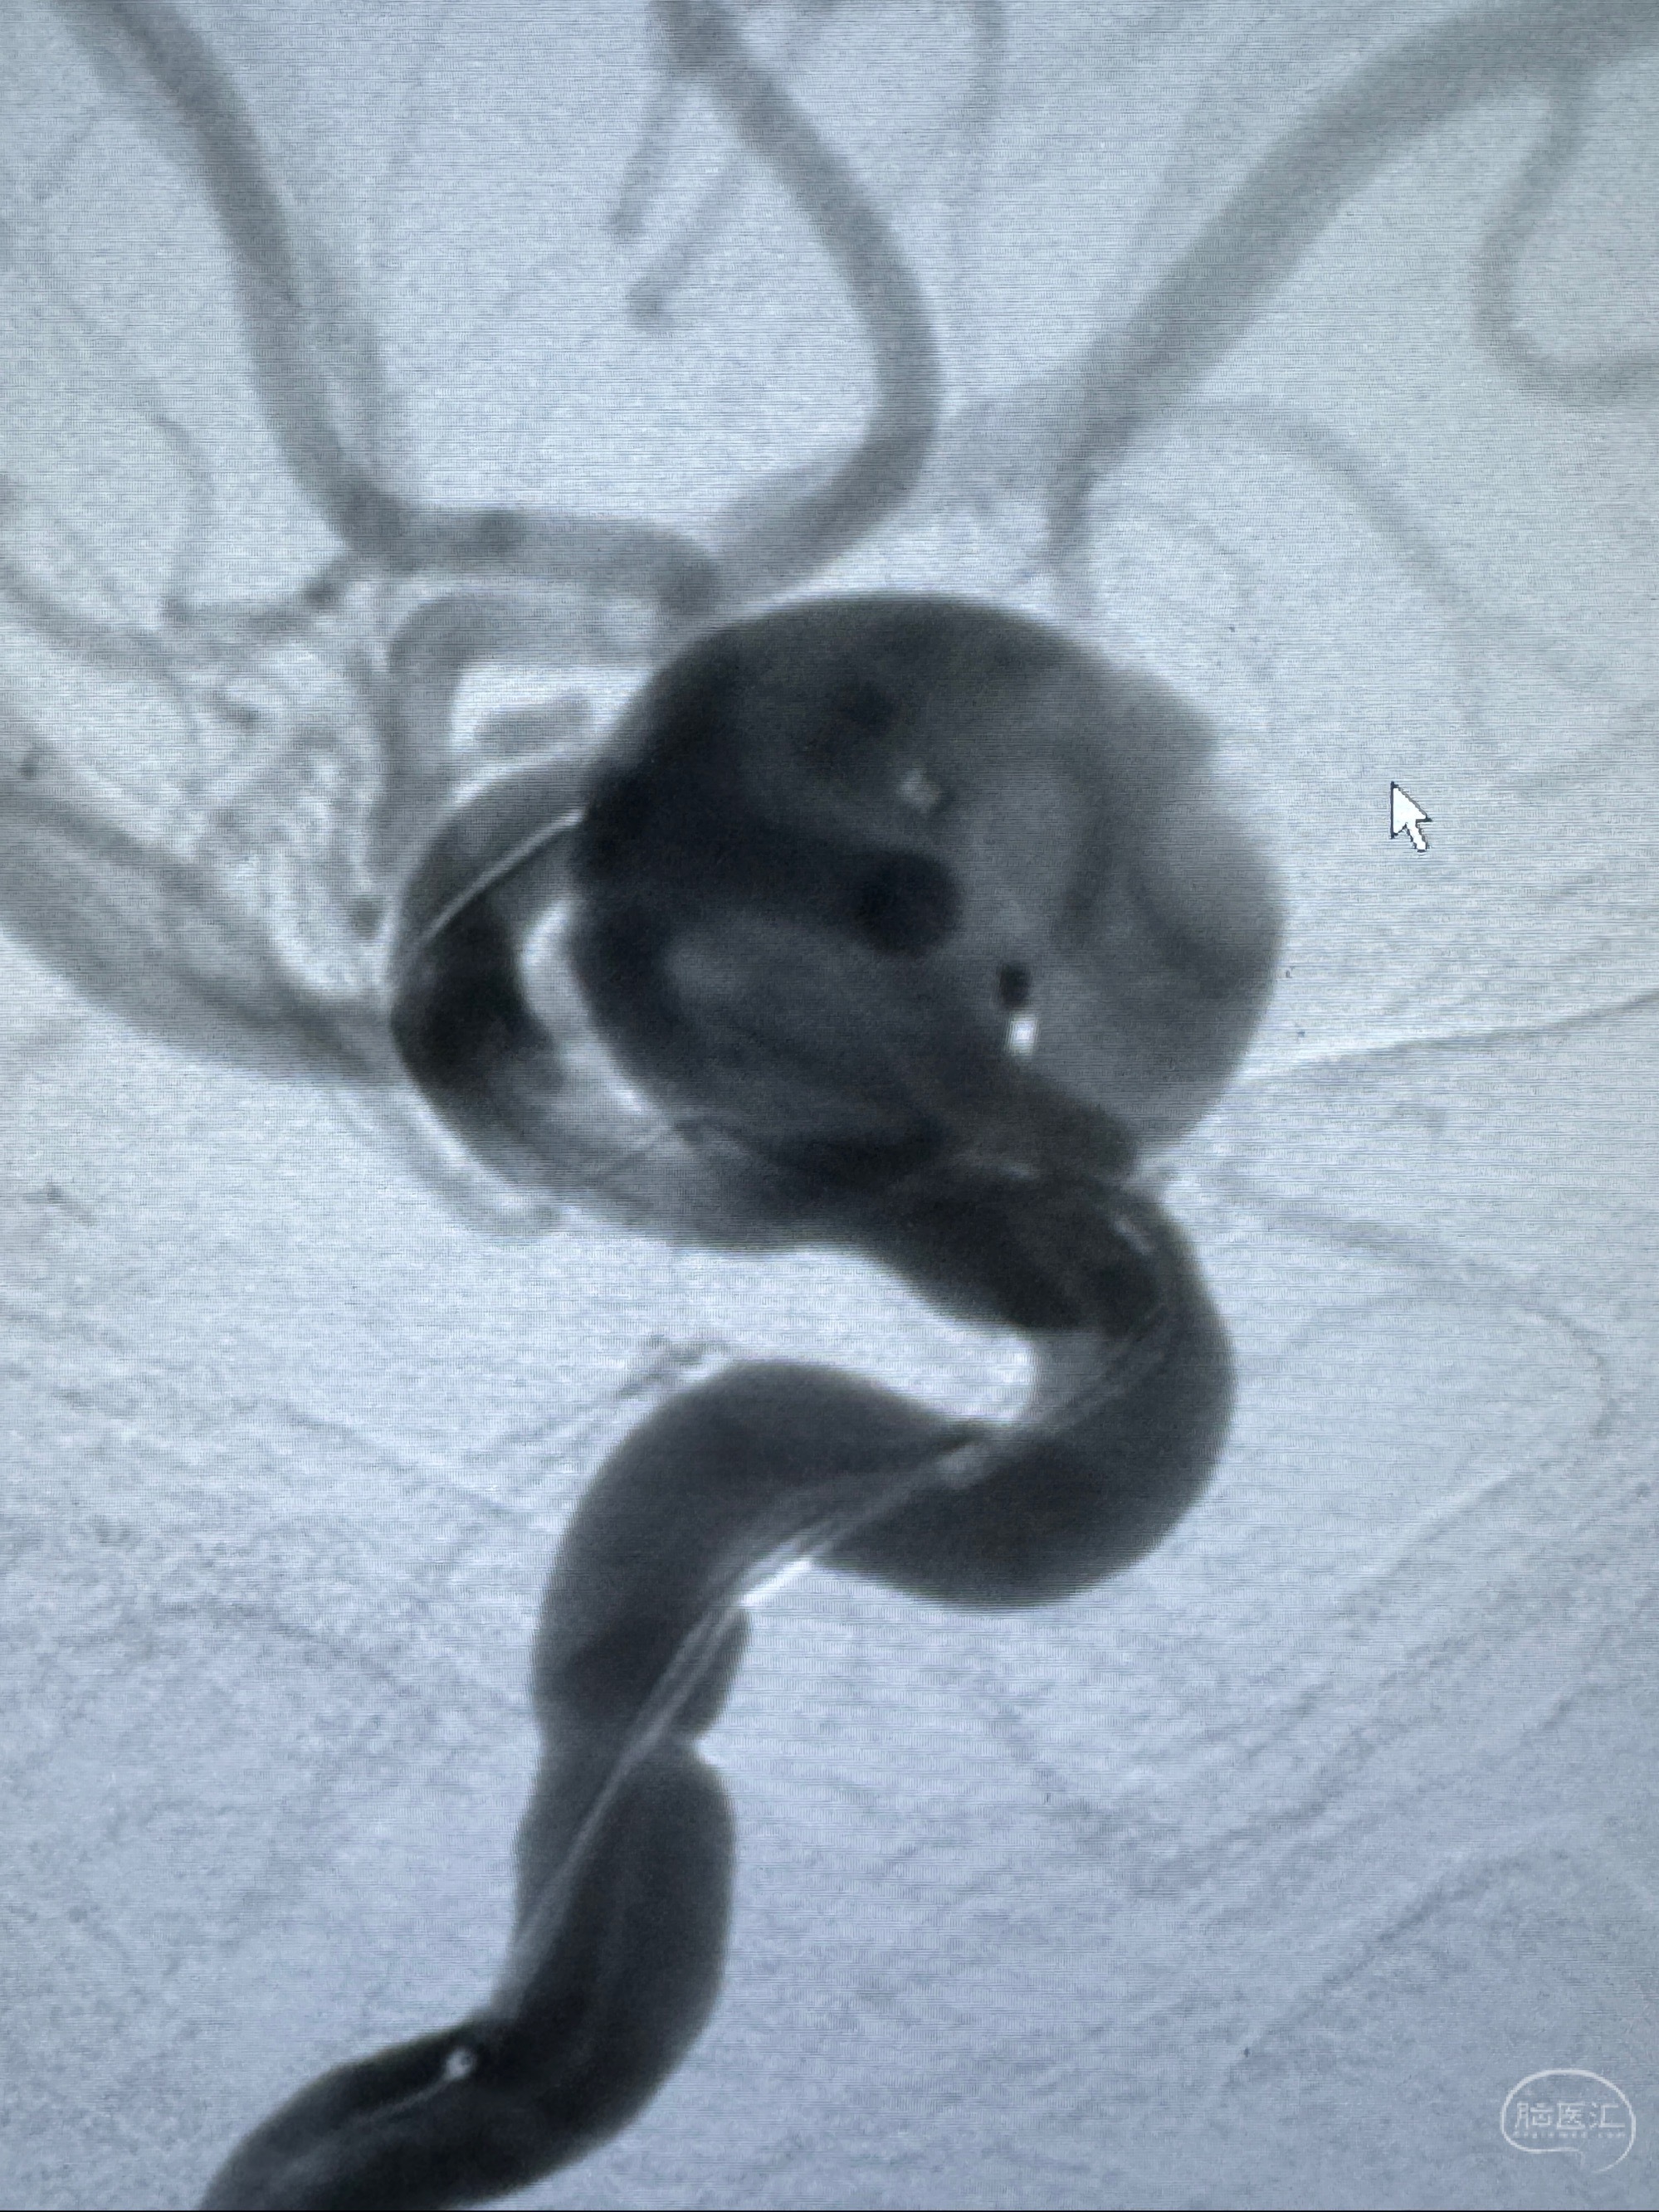

旋转3D展示动脉瘤局部的血管构筑

测量动脉瘤的大小:16*13.8*7.6mm大小,较原先变大,考虑双抗后瘤内血栓溶解可能

观察动脉瘤腔内的血流动力学情况